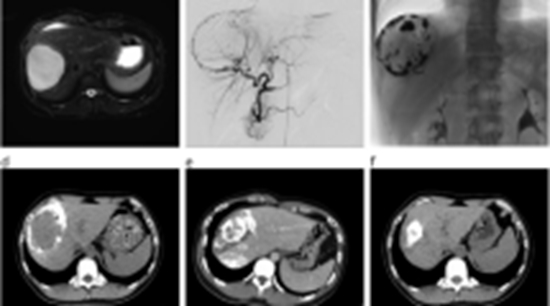

Commentary on Thermal Ablation for Giant Hepatic Hemangiomas: A Meta-Analysis with Subgroup Analysis of Microwave and Radiofrequency Ablation Techniques